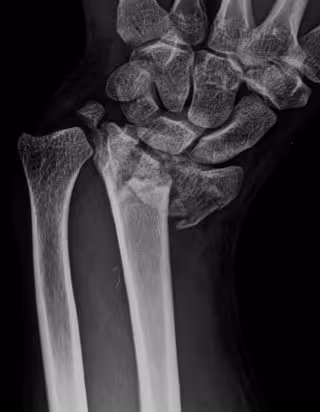

Archivo - Fractura de radio

Archivo - Fractura de radio - HOSPITAL LA LUZ - Archivo